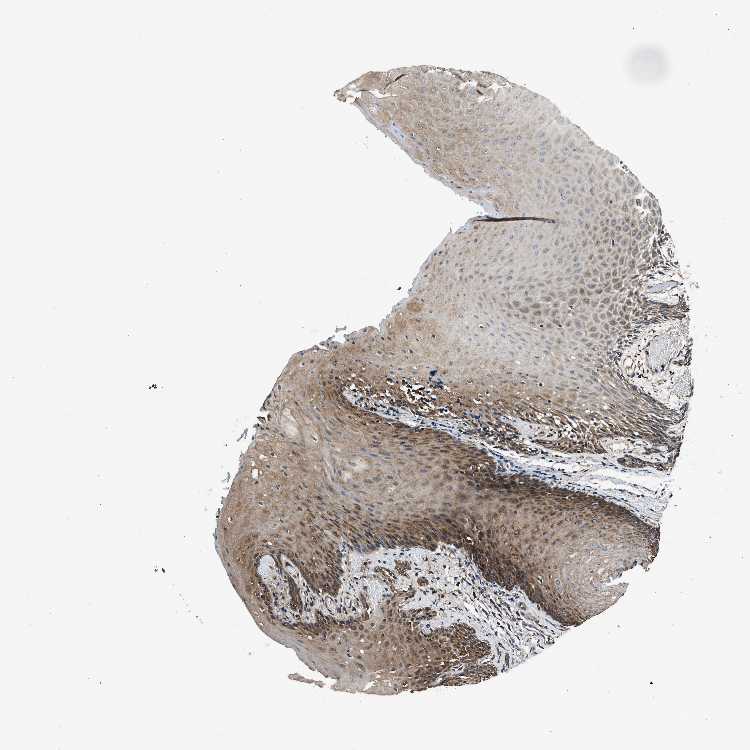

TISSUE PRIMARY DATA ORAL MUCOSA Show tissue menu

ORAL MUCOSA - Antibody stainingi

Antibody staining in the annotated cell types in the current human tissue is reported as not detected, low, medium, or high, based on conventional immunohistochemistry profiling in selected tissues. This score is based on the combination of the staining intensity and fraction of stained cells.

Each image is clickable and will lead to virtual microscopy that enables deeper exploration of all samples and also displays staining intensity scores, fraction scores and subcellular localization as well as patient and tissue information for each sample.

Antibody HPA016649Antibody HPA018152

Squamous epithelial cells MediumHigh